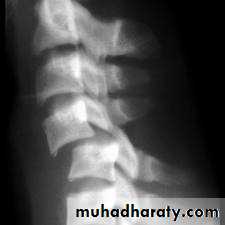

wedge compression fracture of vertebral body

frcature spine and peripheral nerve

Wedge compression fracture of a vertebral body.

WEDGE COMPRESSION FRACTURE

Diagnosis .

obvious symptoms and signs pointing

In cases of major fracture there will be only between the T11 and L2

Treatment

It has been shown that persistent wedging of a vertebral body is compatible. With virtually normal function.

so correction of the deformity is not essential.

The standard method of treatment may, therefore, be said to be conservative.